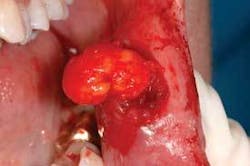

Perioral and intraoral characteristics: Intraorally, lipomas appear as superficial, smooth-surfaced, soft, palpable masses, which often impart a yellowish color to the overlying mucosa (see Figure 2). Note the size of the lipoma and the yellow lobules of adipose tissue evident in this lesion.

Distinguishing characteristics: Oral lipomas are described as having a soft yellow hue with a normal intraoral tissue appearance but appear to be elevated (see Figure 3). Note that the yellow lobular material in the specimen has been removed. Confusion occurs sometimes with the fibroma, which is composed of fibrous tissue and much more firm.